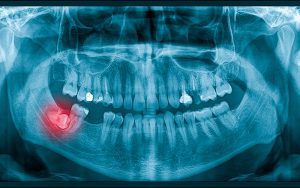

4- hidden or missing teeth

Hidden teeth

The presence of teeth embedded in the jawbone or the early loss of baby teeth can disrupt the natural order of teeth growth. In such a situation, the remaining teeth are moved and the previous teeth are pushed forward. Also, the lack of enough space in the jaw makes the front teeth look protruding.